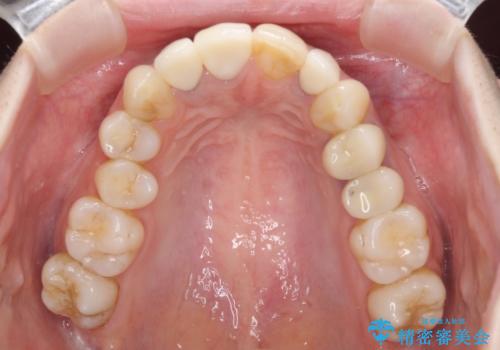

必要な歯には根管治療を行い、金属を使わない土台を植立した上で、オールセラミッククラウンにて補綴することとしました。

色調を統一するために、未治療の1歯もクラウンを装着するかどうか悩んでいらっしゃいましたが、結果としては治療せずに4前歯の色調を合わせることができました。

歯肉の黒ずみも多少改善させることができ、患者様には大変満足していただきました。